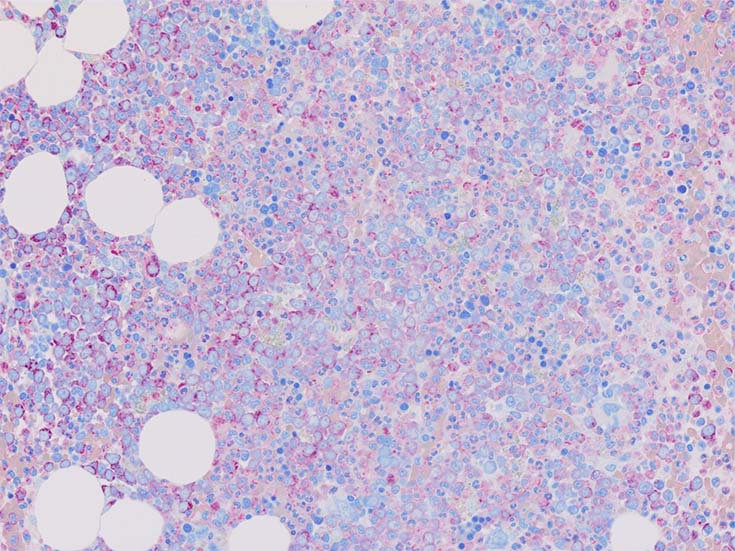

初診時の骨髄組織所見

BM-f-01HE01.jpg BM-f-01HE02.jpg BM-f-01.jpg

HE染色および, Naphtol-ASD-CAE染色した骨髄クロット組織標本-->Naphtol-ASD-CAE染色, 載せガラス法のページをみる.

70-80%のhypercellular marrow. 3系統造血細胞が認められる. Naphtol-ASD-CAE染色で赤色にそまる顆粒球系細胞増生が顕著な骨髄組織.

promyelocytesなど幼若顆粒球系細胞の集簇がみられるが, 分葉好中球他, 成熟顆粒球(Naphtol-ASD-CAE染色は薄く染まる傾向あり)も多く認められacute leukaemiaの所見ではない.

単球(Naphtol-ASD-CAE染色陰性)が密に増殖する所見は骨髄組織には認められない(*1)